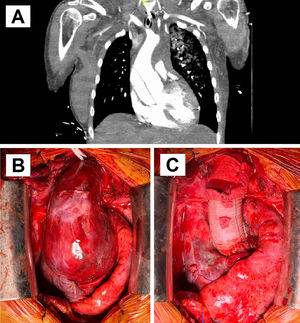

En la ecocardiografía postoperatoria se apreciaba la prótesis aórtica mecánica normofuncionante, con derrame pericárdico moderado que requirió seguimiento, pero sin complicaciones asociadas. En la TC de aorta postoperatoria se confirmó la coartación de aorta posductal severa de 5x3mm con abundante circulación colateral en pared torácica y abdominal secundaria que se dirigía a la aorta postestenosis (fig. 2 A-B). El arco aórtico distal y la aorta descendente poscoartación medían 16-17mm y 20mm, respectivamente, disminuyendo el calibre distalmente que era de 14mm a nivel del diafragma. La paciente presentaba un gradiente de presión arterial mayor a 50mmHg, por lo que se planificó intervención de la coartación en un segundo tiempo.